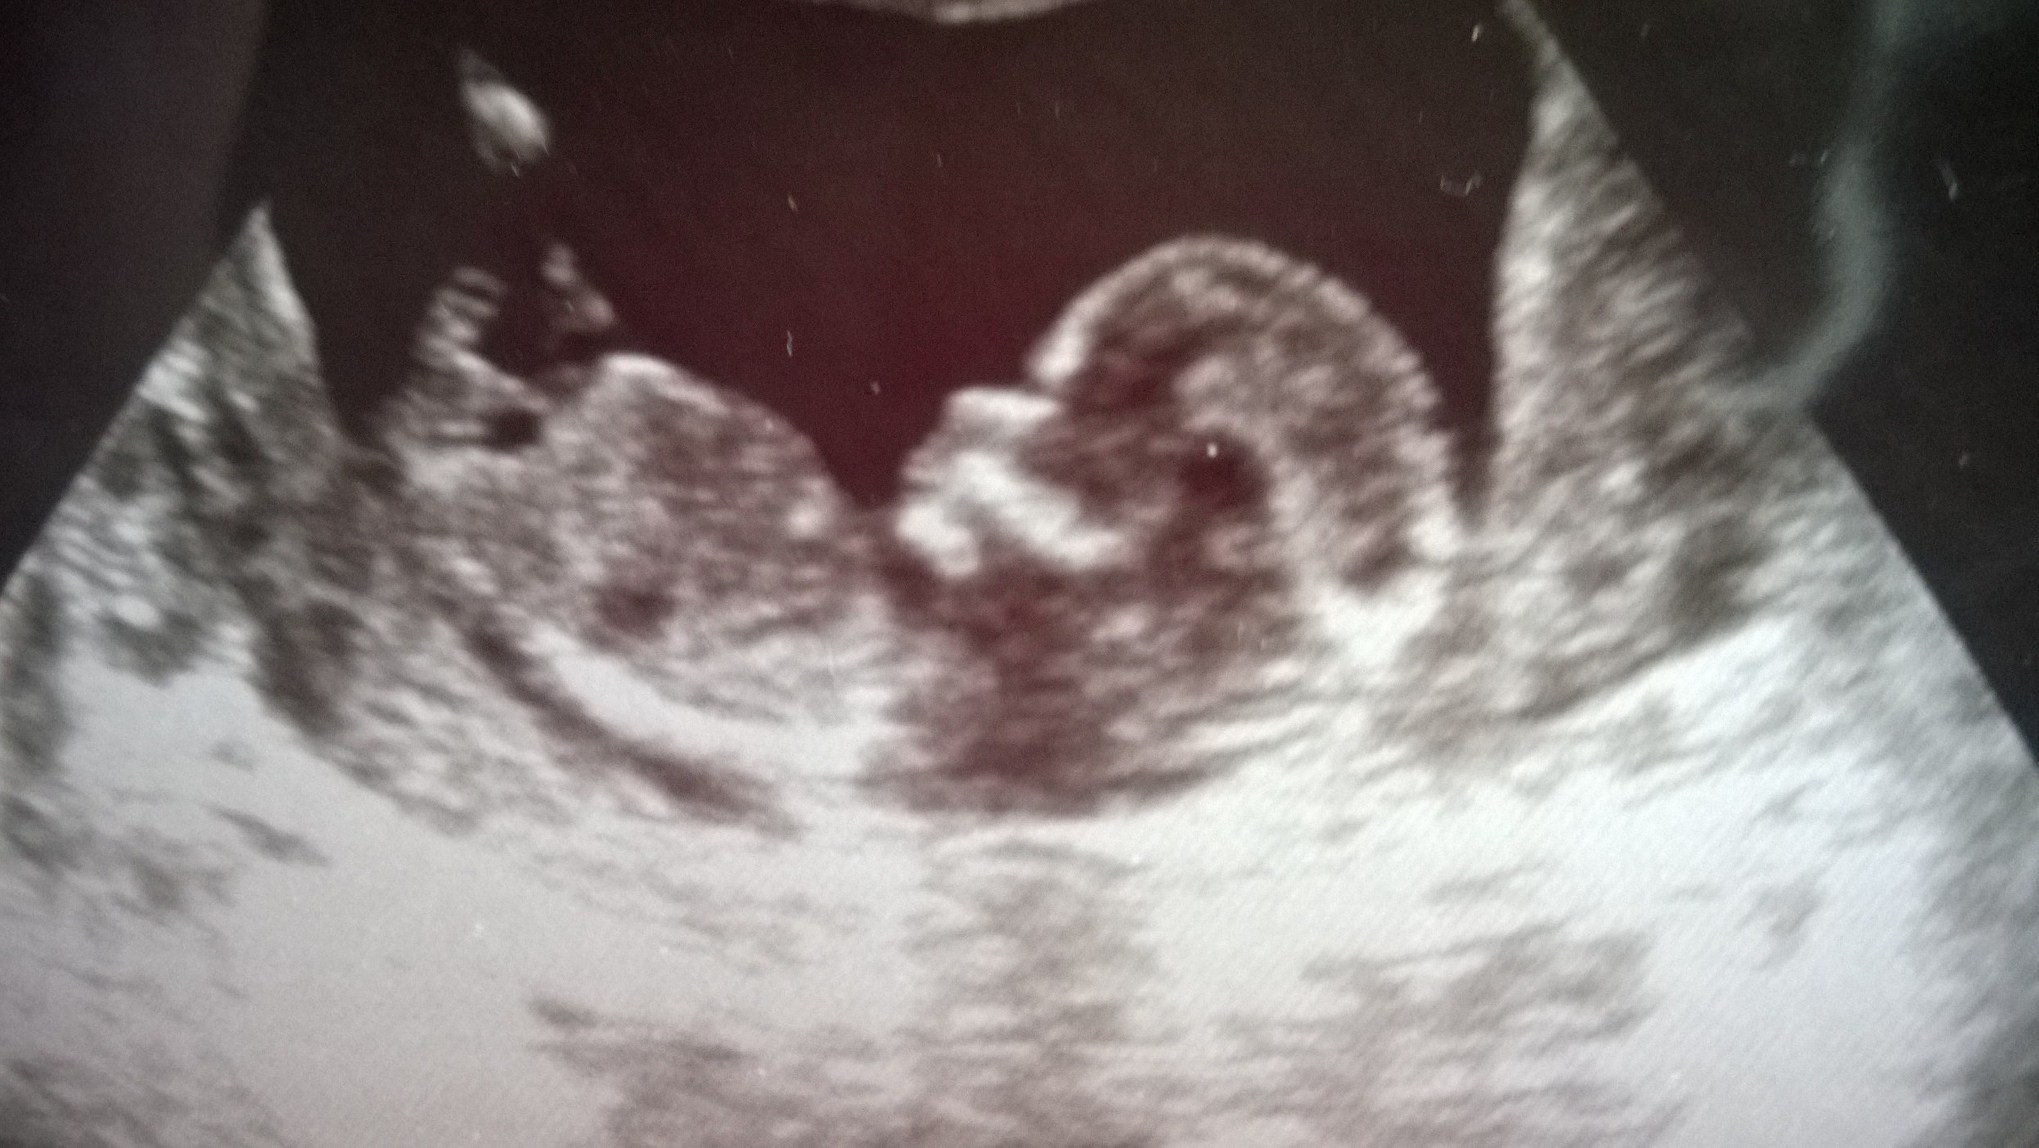

I have no idea how to add to the previous thread. Attachment 19644

Super tricky nub

Someone has to have a guess on the tricky nub

Yah I think girl too although that bump on top is throwing me... But I do think its a seperate thing?!?

Just wanted to update that this was a boy baby. Unfortunately my sister went into preterm labor and lost him. He is our angel now.